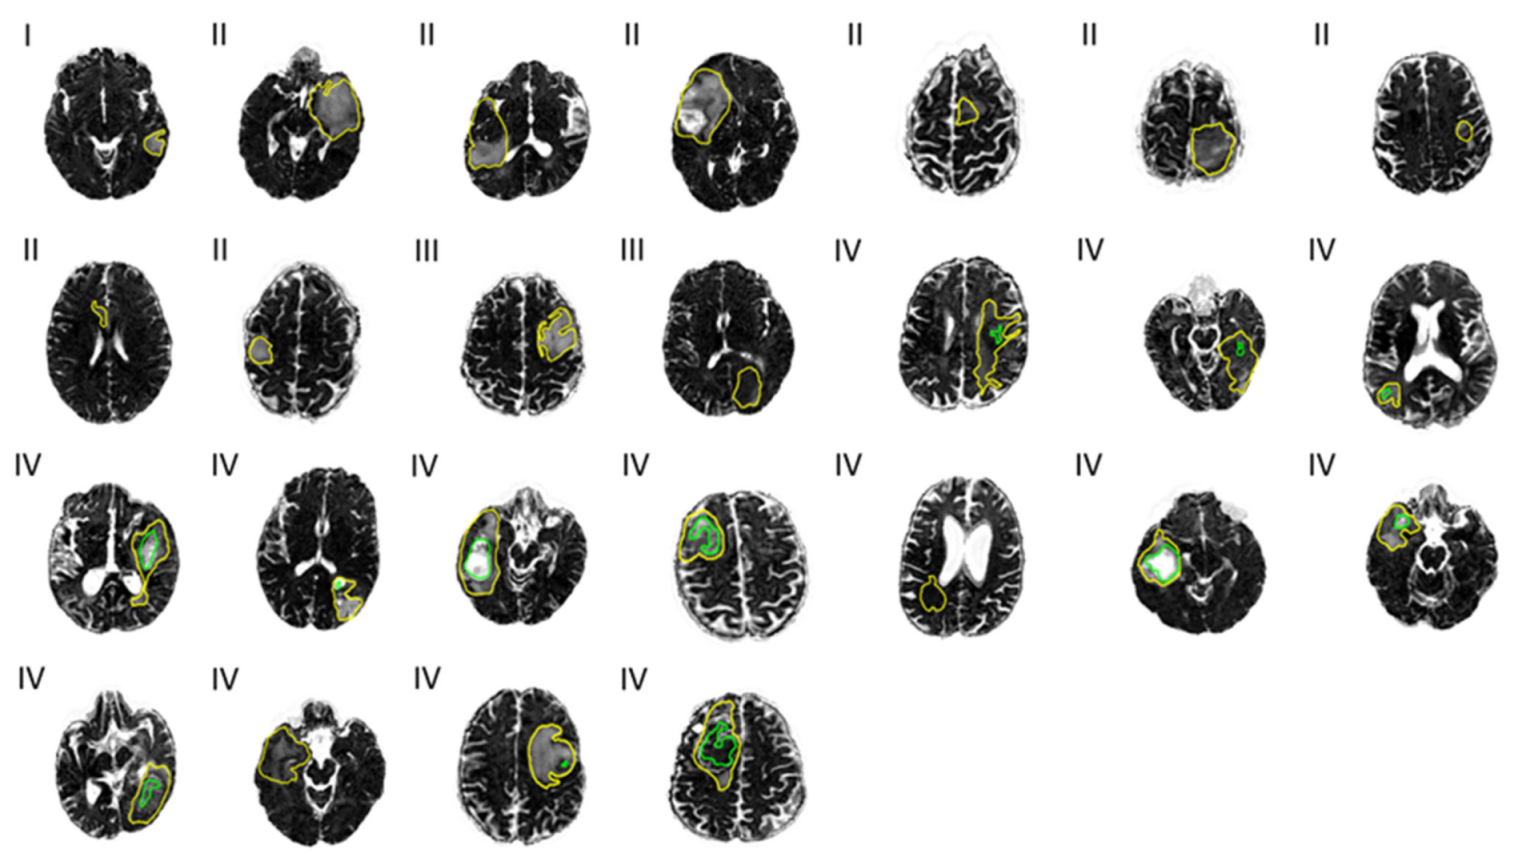

3. Results

3.1. Characterizing Tumor Sub-Regions